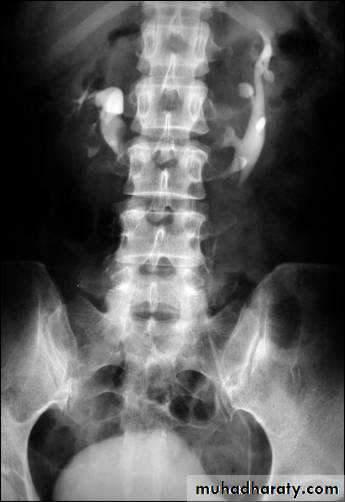

Renal agenesis :

- incidental finding.

- The opposite kidney shows compensatory hypertrophy.

- Can be diagnosed as absent kidney on ultrasound or CT.

- IVU will show a single kidney with active contrast excretion .